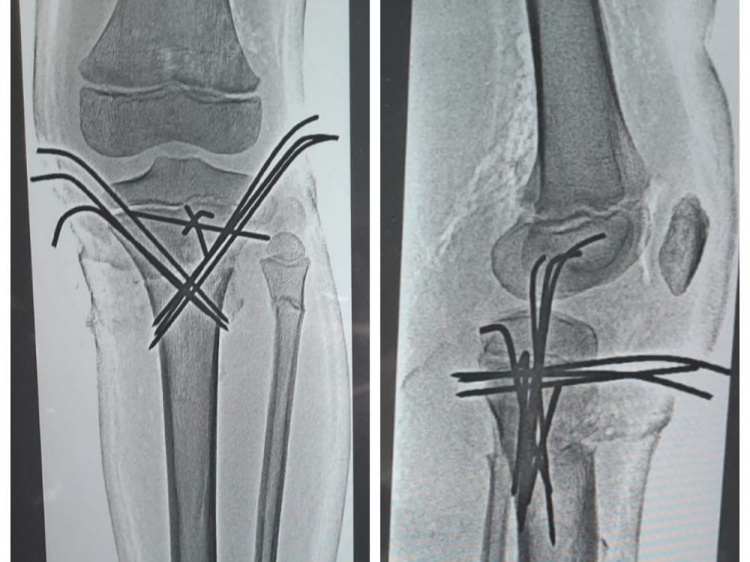

Как сообщили Волжский.ру в комитете здравоохранения, 14-летний школьник попал в серьёзную аварию, столкнувшись с маршруткой. С места аварии его доставили в клиническую больницу скорой помощи №7 в крайне тяжелом состоянии. Врачи диагностировали сочетанную автодорожную травму и травматический шок 2 степени. У юного мотоциклиста насчитали 23 перелома, в том числе закрытую черепно-мозговую травму, перелом ключицы, костей таза со смещением, перелом позвоночника, ушиб легких. Ребенок перенёс уже 4 операции, и до сих пор остаётся в больнице. Ему предстоит ещё несколько хирургических вмешательств по удалению скрепляющих металлических конструкций в конечностях. А после - длительный курс реабилитации.